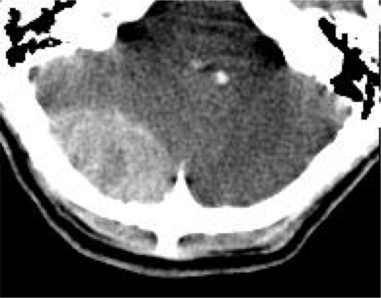

- Comparado con la HSA por rotura de aneurisma, la de origen postraumático suelen se de localización periférica, por encima de los hemisferios cerebelosos.

Hemorragia Intraventricular.